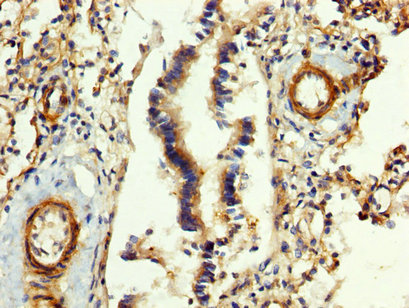

FGB Antibody (CSB-PA008608LA01HU)

IHC image of CSB-PA008608LA01HU diluted at 1:400 and staining in paraffin-embedded human lung tissue performed on a Leica BondTM system. After dewaxing and hydration, antigen retrieval was mediated by high pressure in a citrate buffer (pH 6.0). Section was blocked with 10% normal goat serum 30min at RT. Then primary antibody (1% BSA) was incubated at 4°C overnight. The primary is detected by a biotinylated secondary antibody and visualized using an HRP conjugated SP system.